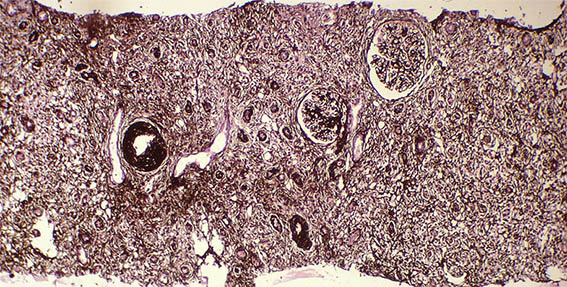

Figure 7. Methenamine-silver stain, X100.

Figure 8. Methenamine-silver stain, X400. Glomeruli with normal characteristics.